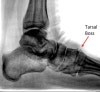

족근골 혹(Tarsal boss) : 꽉 끼는 구두의 끈을 조이면 발등이 아프고, 좀처럼 좋아지지 않아요

Lisfranc 관절이나 Chopart 관절의 골극으로, 배측에 골융기를 발생시킵니다.

신발에 닿아 통증을 호소하고, 가끔 bursitis나 entrapment를 일으키는 원인이 됩니다.